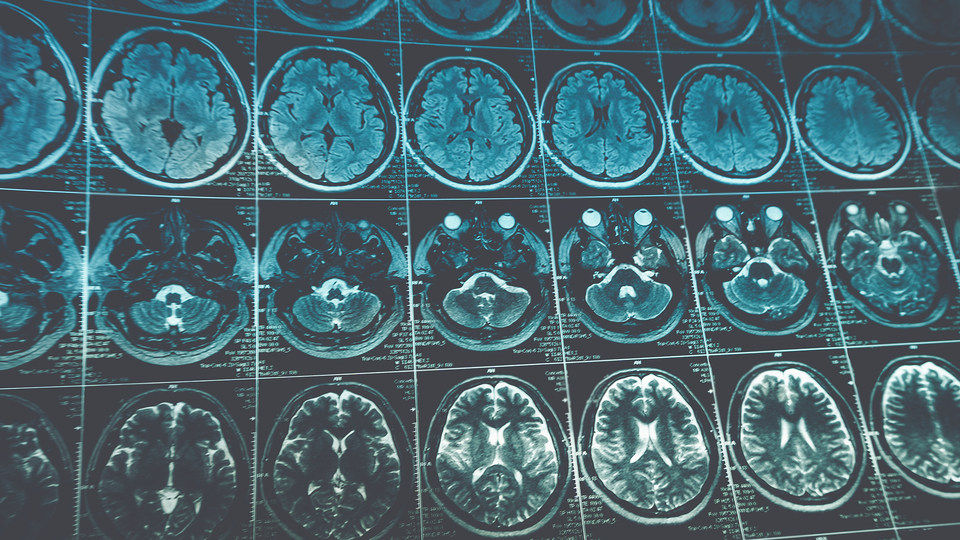

Bilim insanları, geliştirdikleri yeni yapay zeka yazılımı aracılığıyla inme geçiren hastaların beyin taramalarında inmenin ne zaman geçirildiği ve tedavi edilip edilemeyeceğinin normalden 2 kat daha doğru tespit edilebildiğini açıkladı

Araştırmacılar yazılımın, beyin taramasında ilgili alanı otomatik olarak çıkarmanın yanı sıra, tanımlanan lezyonları analiz ederek inme geçirilen zamanı tahmin edebildiğini tespit etti.

Araştırmacılar, yeni yapay zeka yazılımı kullanılarak yapılan taramaların doku gibi ek özellikler içermesi ve lezyonlardaki varyasyonları hesaba katmasının daha önce kullanılan tarama yöntemlerine kıyasla daha iyi sonuç alınmasında etkili olduğunu belirtti.